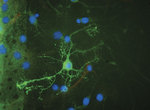

Dental pulp stem cells are highly promising as precursors of replacement neurons (brain cells) because they are easily accessible, can be taken from the patient needing treatment, and they have similar properties to cranial neural crest cells that normally make brain cells and other cranial tissues.

A neural cell derived from an adult stem cell

Image courtesy of the Centre for Stem Cell Research